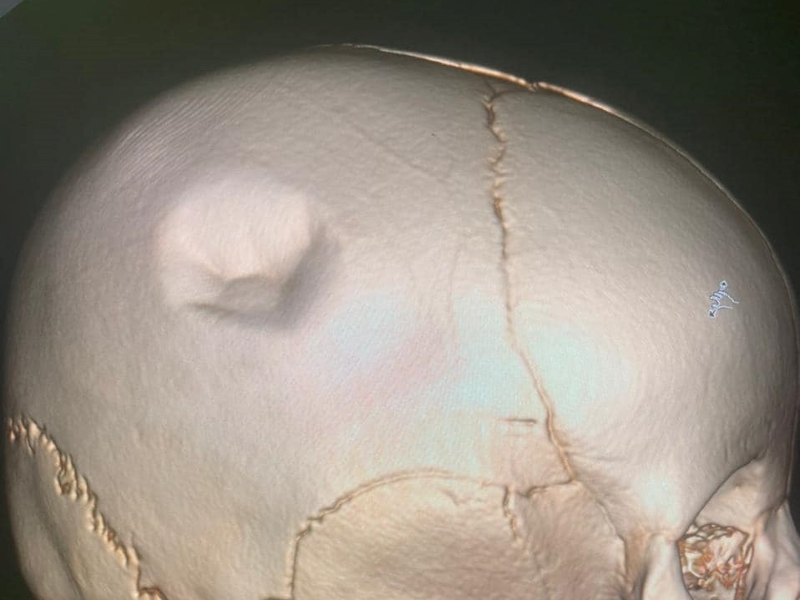

Шестимесячному ребенку провели трепанацию черепа в Мангистауской области. Состояние малыша стабилизировалось, передает Kazpravda.kz со ссылкой на портал «Мой ГОРОД».

В Мангистауской областной детской больнице рассказали, что вечером 20 апреля в экстренном порядке в приёмный покой доставили шестимесячного малыша с вдавленным переломом теменной кости.

«По словам родителей, четырёхлетний старший брат по неосторожности пнул его в голову. Детский нейрохирург Ербол Кенжевалов провёл успешную трепанацию черепа», – рассказали в больнице.

Состояние ребёнка оценивается как средней тяжести.